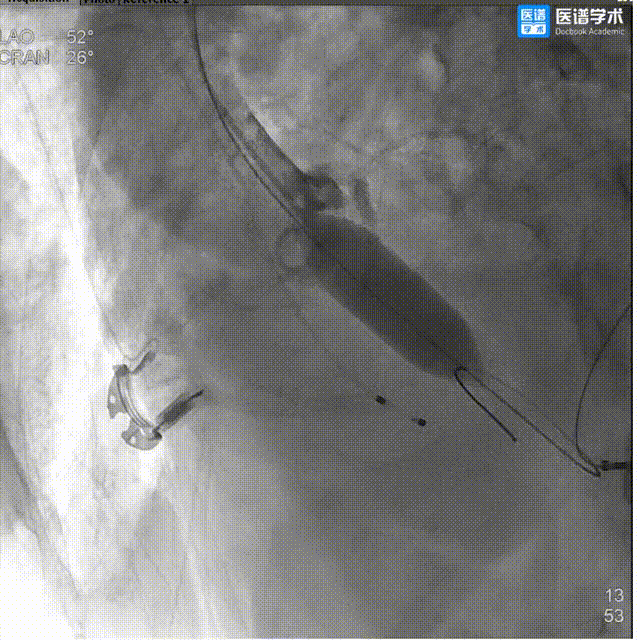

4、180次/分快速起搏下以22mm 球囊进行第一次预扩张,扩张同时造影示明显腰征,球囊受挤压上跳。扩张后超声示跨瓣压差37mmHg,峰值流速303cm/s,主动脉狭窄情况得到改善,主动脉瓣叶活动性增强;

5、180次/分快速起搏下以22mm 球囊进行第二次预扩张,扩张同时造影示明显腰征,球囊受挤压下滑,右冠显影不明显,考虑灌注不良,超声示两次球扩未造成患者主动脉根部明显损伤变形;